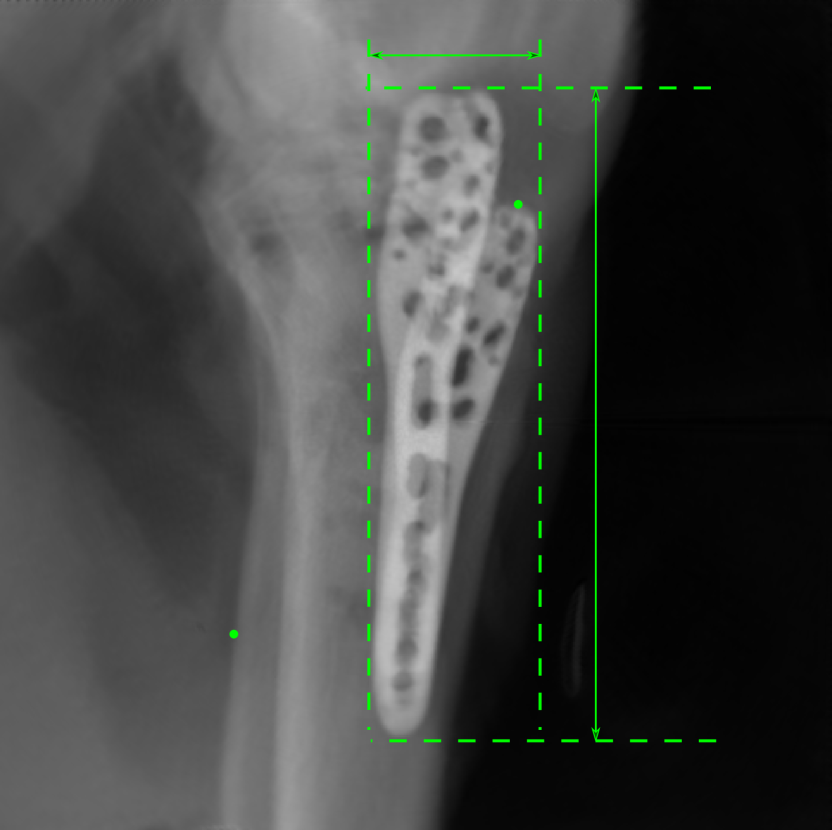

Figure 14: The results for the real cadaver leg data. The green dots mark the positions of landmarks in the corresponding reference images. In the first column, the arrows indicate the bone cavity/fracture structures. In the second column, the solid lines mark the widths and heights of the metals. The green ones are measured from the DRR reference, while the red ones are measured in the corresponding perspective projection image. In the last column, the lines mark the centerlines of the metal screws, where the green lines are those from the reference image. The lengths of the lines in mm are displayed in their corresponding subcaptions. Intensity window: [0, 4]. Please zoom in for better visualization.

The complementary view setting for learning perspective deformation is also evaluated on real CBCT projection data. In this evaluation, real CBCT projection data from a dataset of knees with metal implants is used for testing, while DRRs created from volumetric CT datasets with inserted metals is used for training. Three exemplary DRR perspective projection images for training are displayed in Fig. 13, in which synthetic metal implants are inserted [34]. The appearance, e.g., image contrast and metal image resolution, of such DRR training images is different from that of real projection images in Fig. 14. In Fig. 14, the results for three knees, with and without metal implants, are displayed. The first and second rows are the 0superscript00^{\circ} and 180superscript180180^{\circ} perspective projections, respectively, rebinned to the virtual detector with geometric calibration based on their respective principal points and projections of the world origin. The third row displays their difference images, where the magnitude of deviation increases from the center towards the outside like it does in DRRs with an ideal scan trajectory (e.g., Fig. 6(e)), although real projection data suffer from various physical effects like beam hardening and Poisson noise. The fourth row displays the RGB stacks of 0superscript00^{\circ} and 180superscript180180^{\circ} perspective projection images. The magenta and green regions indicate structures with considerable perspective deformation, for example, the knee patella in Fig. 5.4, the top parts of the two metals in Fig. 5.4, and the bottom two screws in Fig. 5.4. The fifth row displays reference images, which are orthogonal projections of iterative reconstruction volumes from measured CBCT projection data. In the reference images, a total of five landmarks are selected, with the positions being marked by the green dots: In Fig. 5.4, two positions at the edges of the knee patella are marked; In Fig. 14(e) and Fig. 14(f), one position at the left edge of the fibula is marked for each image. In addition, a rectangular frame for the two metals is marked by the green dashed lines, while its width and height are indicated by the green solid lines, which are 29.71 mm and 111.99 mm, respectively. In Fig. 14(f), the centerlines of the bottom two screws are sketched by the green lines, which have the lengths of 17.14 mm (middle screw) and 19.38 mm (bottom screw). The corresponding rectangular frame for the two metals and the screw centerlines in the perspective projection images are marked as well, but in red color. In Fig. 14(a), the width and height of the metals are 32.56 mm and 109.85 mm, which have deviations of 2.84 mm and -1.95 mm to the reference ones, respectively. In Fig. 14(b), the centerline lengths are 18.91 mm and 19.54 mm, which have deviations of 1.77 mm and 0.16 mm, respectively. Although the bottom screw has little length deviation to the reference, the orientations of both screws are obviously deviated. The sixth row shows the results of Pix2pixGAN using 0superscript00^{\circ} and 180superscript180180^{\circ} polar inputs. For all of the landmarks, the green reference dots are all located accurately in the Pix2pixGAN images. The rectangular reference frame also accurately covers the metals in Fig. 14(g). In Fig. 14(h), although the two red centerlines do not exactly overlap with the green one, they are very close in lengths and orientations. Please zoom in for better visualization.